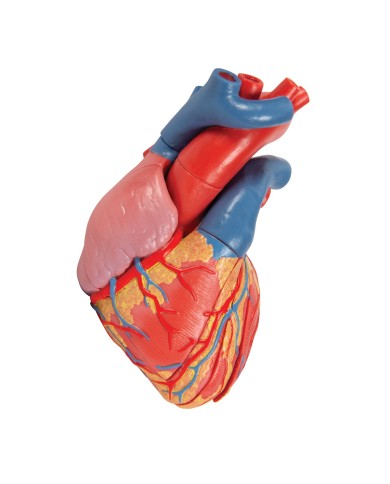

Modello di cuore di alta qualità scomponibile in 5 parti

Modello di cuore di alta qualità scomponibile in 5 parti

Modello anatomico di cuore, ingrandito 2 volte, su cavalletto

Realizzato in stampa 3D ad elevatissima risoluzione a colori.